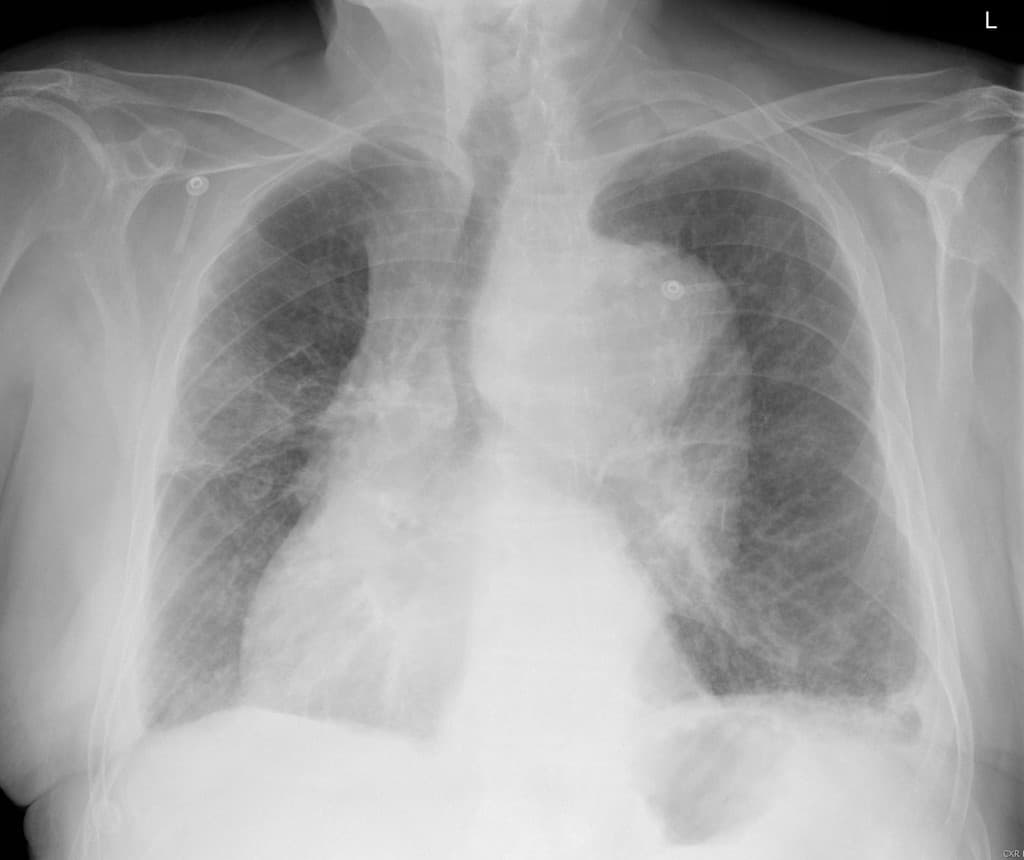

Đột quỵ. Rung nhĩ. Đau ngực. Siêu âm tim (cardiac US): giãn động mạch chủ lên. Cần thực hiện chụp CT để loại trừ phình tách động mạch chủ (aortic dissection).

- Nhĩ trái giãn, kèm dày vách liên thuỳ và dày quanh phế quản - mạch máu, phù hợp với phù do tim nhẹ (mild cardiogenic edema).